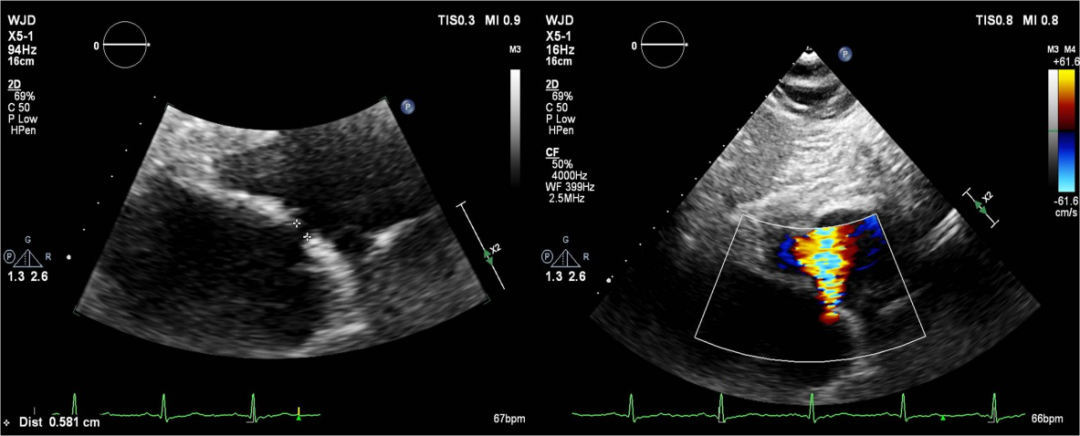

图解:超声心动图提示,术后通过所造房间隔瘘口,房水平可见左向右分流。